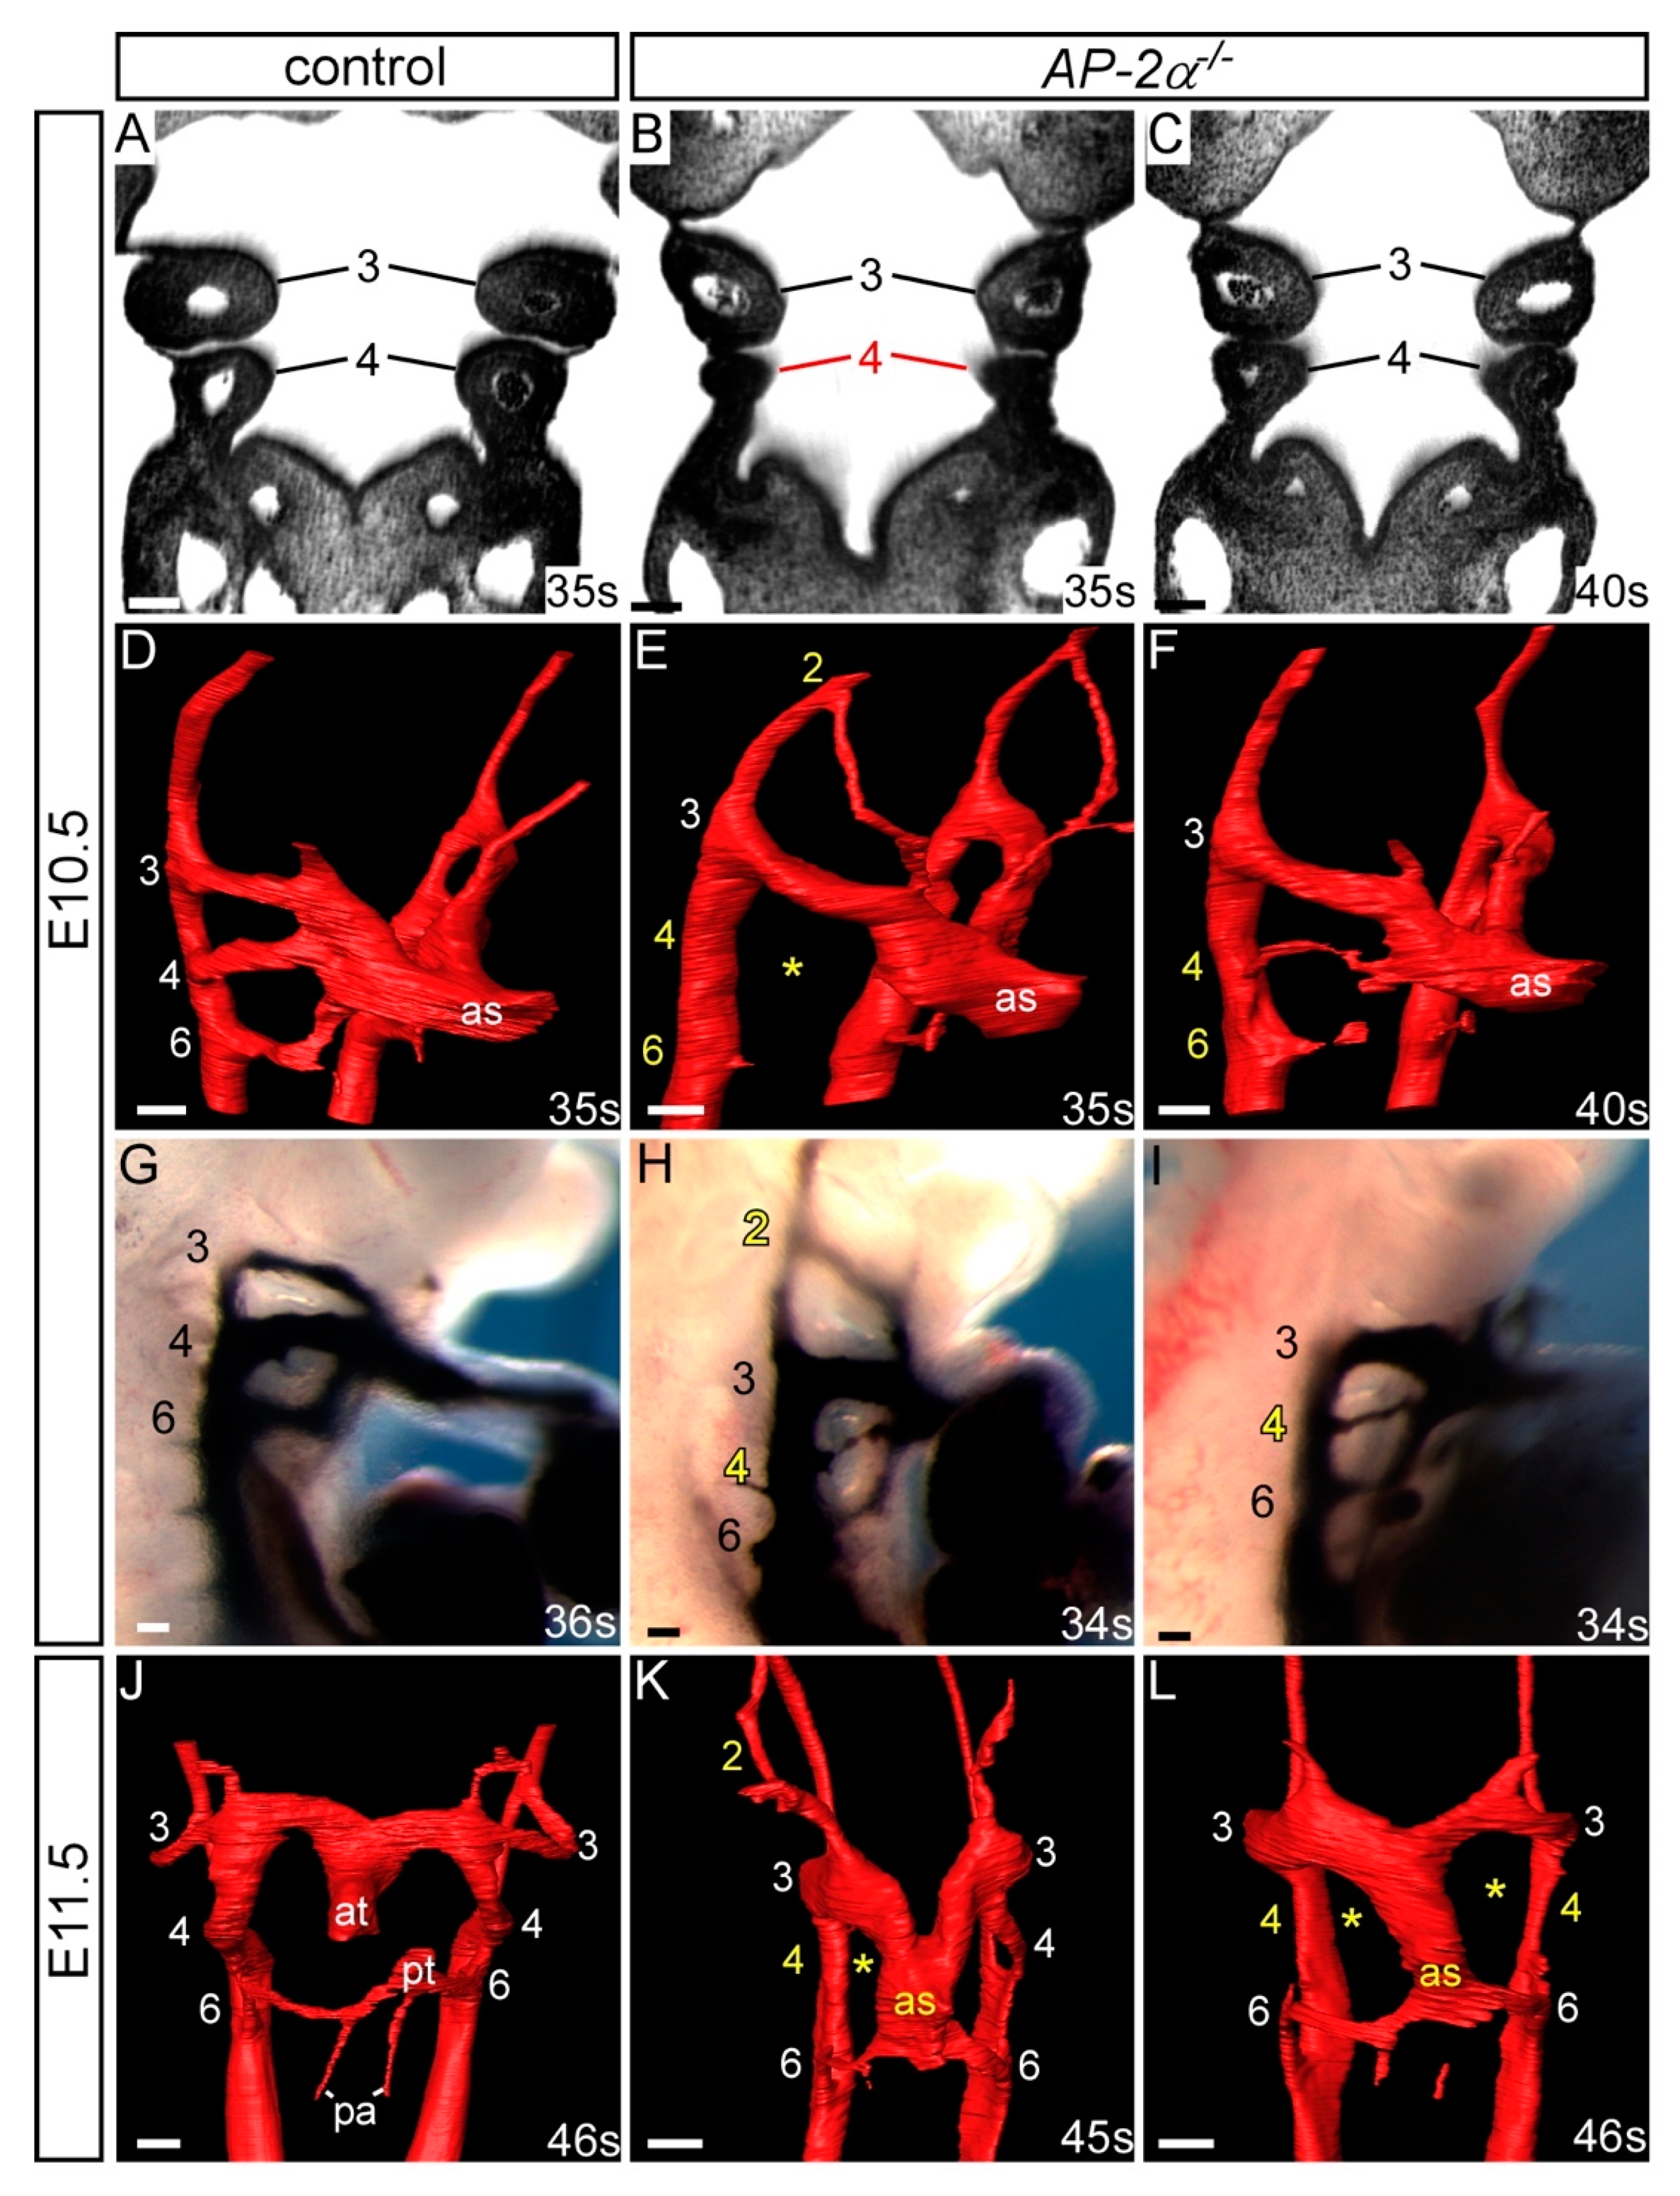

3.1. Cardiovascular Phenotype in C57Bl/6J AP-2α−/− Embryos